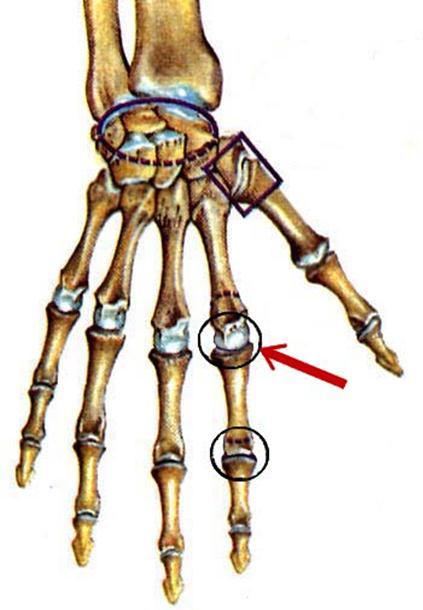

S: Стрелка указывает на art....

S: Стрелка указывает на art....

S: Стрелка указывает на art....

S: Стрелка указывает на art....

S: Стрелка указывает на art....

S: Стрелка указывает на art....

S: Стрелка указывает на art....

S: Стрелка указывает на art....

S: Стрелка указывает на art....